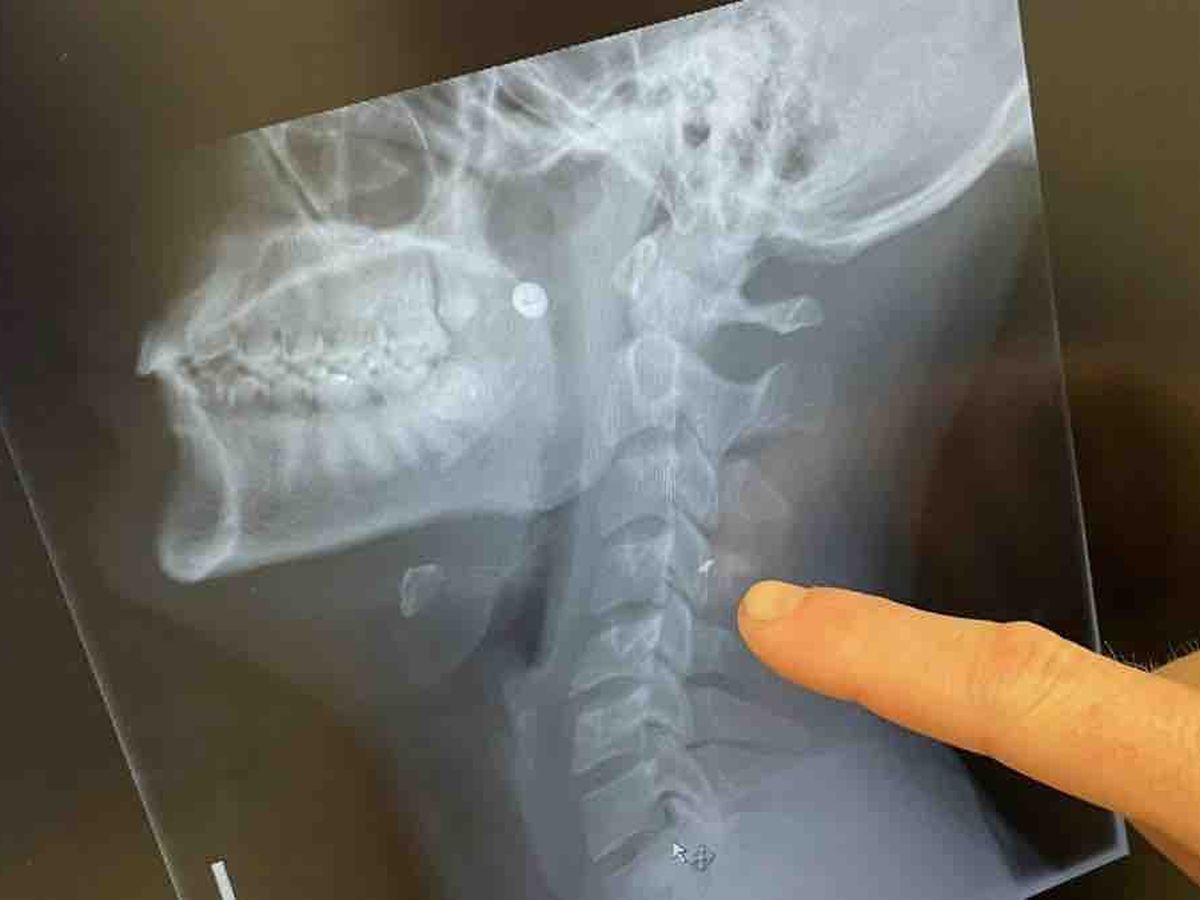

Last Thursday, September 21, Hernán was inside his house and a gunfight broke out outside. one of them entered and hit his face and broke into 4 splinters, one of them is inside his spine, we have incurred considerable expenses (doctor and lawyer) since those involved in the shooting fled and there is no responsible captured for now. For those who know Hernán, he is an athlete by profession and a beautiful human being. He will not be able to work for a few months since he must generate bone callus around the splinter, so he must keep completely still. this is the reason why we now ask you for financial help so that this bird returns to the skies